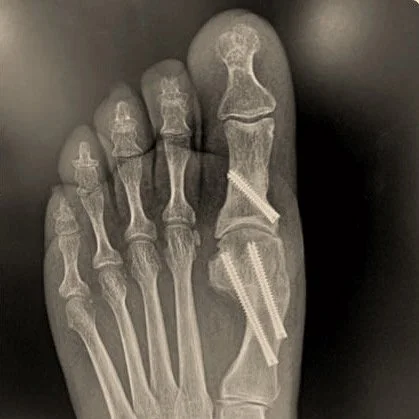

Bunion Correction and Forefoot Procedures Bunion Correction Bunion Correction 1st MTP joint decompression osteotomy 1st MTP joint decompression osteotomy Cheilectomy Cheilectomy Plantar Plate Repair Plantar Plate Repair 5th Metatarsal Osteotomy (Bunionette Correction) 5th Metatarsal Osteotomy (Bunionette Correction) Metatarsal Osteotomy Metatarsal Osteotomy Hammertoe Correction Hammertoe Correction Sesamoidectomy Sesamoidectomy